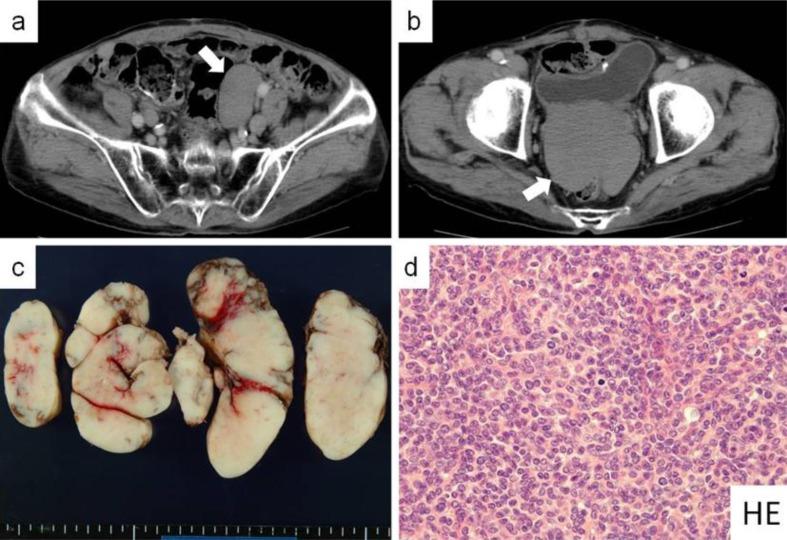

An 83-year-old man underwent complete resection of a large malignant solitary fibrous tumor in the retroperitoneum in 2006 and of a local recurrent tumor in 2010. In 2011, he was admitted to our hospital because of hypoglycemia. His serum glucose level was very low, and his levels of insulin and C-peptide were low. Furthermore, he had a recurrent tumor in the retroperitoneum and pelvis. Immediately after the third surgery for complete resection, he had no hypoglycemic episodes and his serum glucose level was within the normal range. Immunoblotting analysis revealed a high-molecular-weight form of insulin-like growth factor II in the patient's serum and in the protein extract obtained from the resected specimen in 2011. To our knowledge, this is the first report of non-islet cell tumor hypoglycemia caused by a malignant solitary fibrous tumor secreting a high-molecular-weight form of insulin-like growth factor II at the second recurrence.

一名83岁男性在2006年接受了腹膜后巨大恶性孤立性纤维瘤的完整切除,并于2010年接受了局部复发性肿瘤的切除。2011年,他因低血糖入住我院。他的血清葡萄糖水平非常低,胰岛素和C肽水平也很低。此外,他在腹膜后和骨盆有复发性肿瘤。在第三次完整切除手术后,他立即没有低血糖发作,血清葡萄糖水平在正常范围内。免疫印迹分析显示,患者血清以及2011年从切除标本中获得的蛋白质提取物中存在高分子量形式的胰岛素样生长因子II。据我们所知,这是首例由分泌高分子量形式胰岛素样生长因子II的恶性孤立性纤维瘤在第二次复发时引起的非胰岛细胞瘤低血糖症的报告。